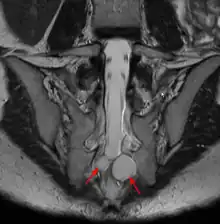

Un kyste de Tarlov (KT) ou kyste périneural, est une dilatation locale de l'espace sous-arachnoïdien se formant au contact d'une racine nerveuse, le plus souvent sacrée, dans la zone de transition entre arachnoïde et périnèvre (membrane externe du nerf). Il est fréquent et le plus souvent asymptomatique, mais peut parfois causer des symptômes neurologiques : on parle alors de maladie de Tarlov.

Le kyste de Tarlov est le plus souvent asymptomatique et découvert fortuitement lors du bilan d'imagerie d'une lombosciatique[5]. Cependant le kyste en lui-même peut être une cause de sciatique, voire lorsqu'il est situé au niveau sacré de troubles vésicosphinctériens (mictions impérieuses, dysesthésie anale...)[5]. Chez la femme, le kyste de Tarlov peut être la cause d'un syndrome d'excitation génitale persistante[6].

Quel que soit le système de classification, la définition d'un kyste de Tarlov est histopathologique car elle nécessite la présence de fibres de racines nerveuses de la colonne vertébrale dans la paroi du kyste ou dans sa cavité. Les kystes de Tarlov sont définis comme des lésions sacciformes, remplies de LCS, situées dans l'espace extradural du canal spinal sacré et formées à l'intérieur de la gaine de la racine nerveuse au ganglion de la racine dorsale.